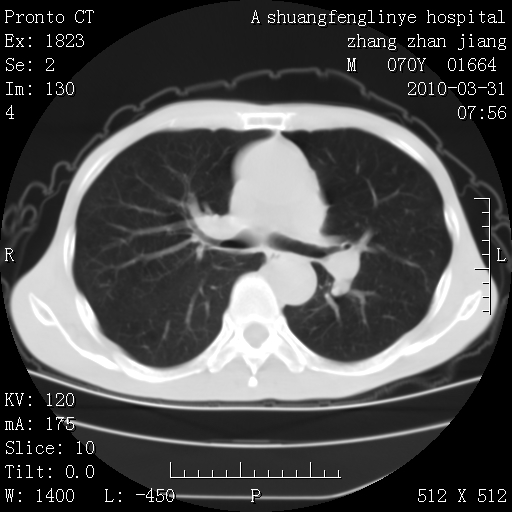

双上肺继发型tb并左上空洞形成,主动脉冠脉钙化。

1)两肺上叶继发性肺结核并左肺上叶空洞形成。2)冠状动脉及主动脉钙化。